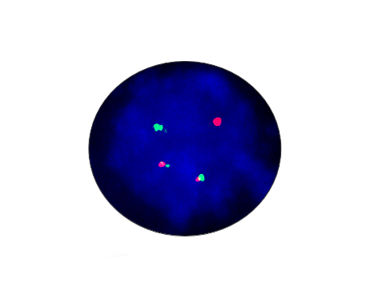

- FISH

1.非小細胞肺がんでは、inv (2) (P21; P23)が融合遺伝子EML4-ALKの分子サブユニットを形成し、標的薬Crizotinibのターゲットとなっています。

2.2010年の非小細胞肺がん診療ガイドラインでは、ALK阻害剤の効果予測のために、新たにEML4-ALKの評価項目が追加されました。